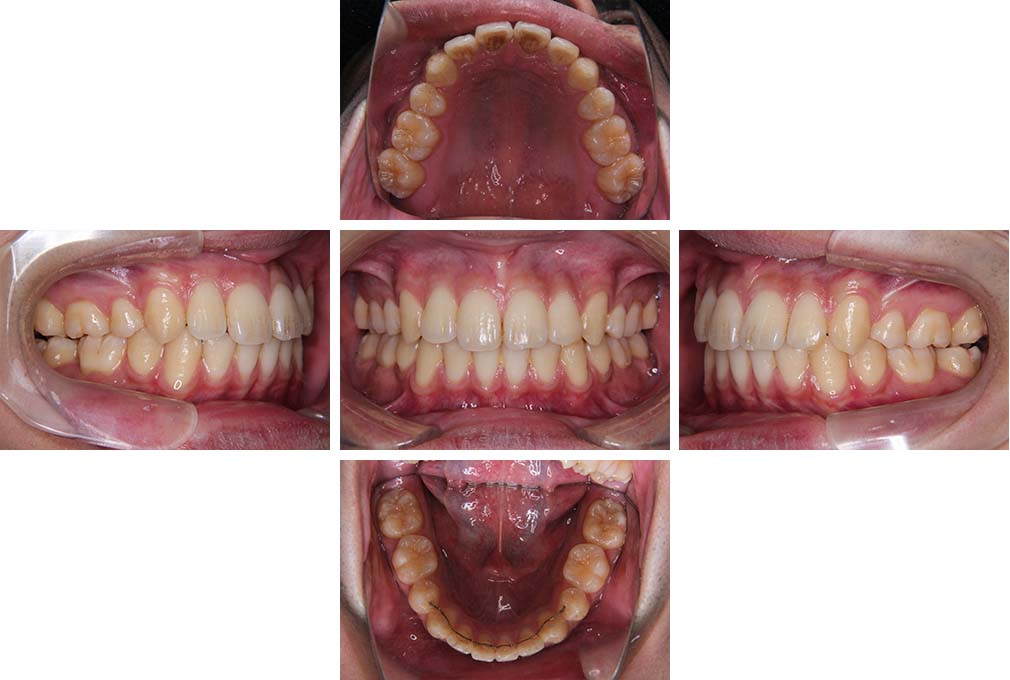

CASE:02

下顎前歯部叢生、小臼歯4歯先天欠損

初診時年齢 14歳3か月

性別 女性

治療費の目安 70万円(治療開始時)

上顎左右側小臼歯3歯、下顎左側第二小臼歯の先天欠損と下顎前歯の叢生を主訴として近隣一般歯科から紹介来院した。

上顎左側第一、第二小臼歯、右側第一小臼歯、下顎左側第二小臼歯が先天欠損であったが、左上第二乳臼歯の根の吸収がほぼ無いことから、これを残すこととして、下顎左側乳臼歯と、右側第二小臼歯を抜歯していただきマルチブラケット装置を使用して動的治療を行った。矯正用ゴムなどの協力状態も良く2年0カ月(調整来院19回)で装置を撤去し保定へ移行した。動的治療終了13年2カ月での来院時には下顎左右側智歯が萌出していたが、垂直的に萌出していたため抜歯は行っていない。

治療前

14歳3か月

治療後

動的治療期間2年0カ月

16歳7か月

13年経過

動的治療終了後13年2カ月

30歳0か月